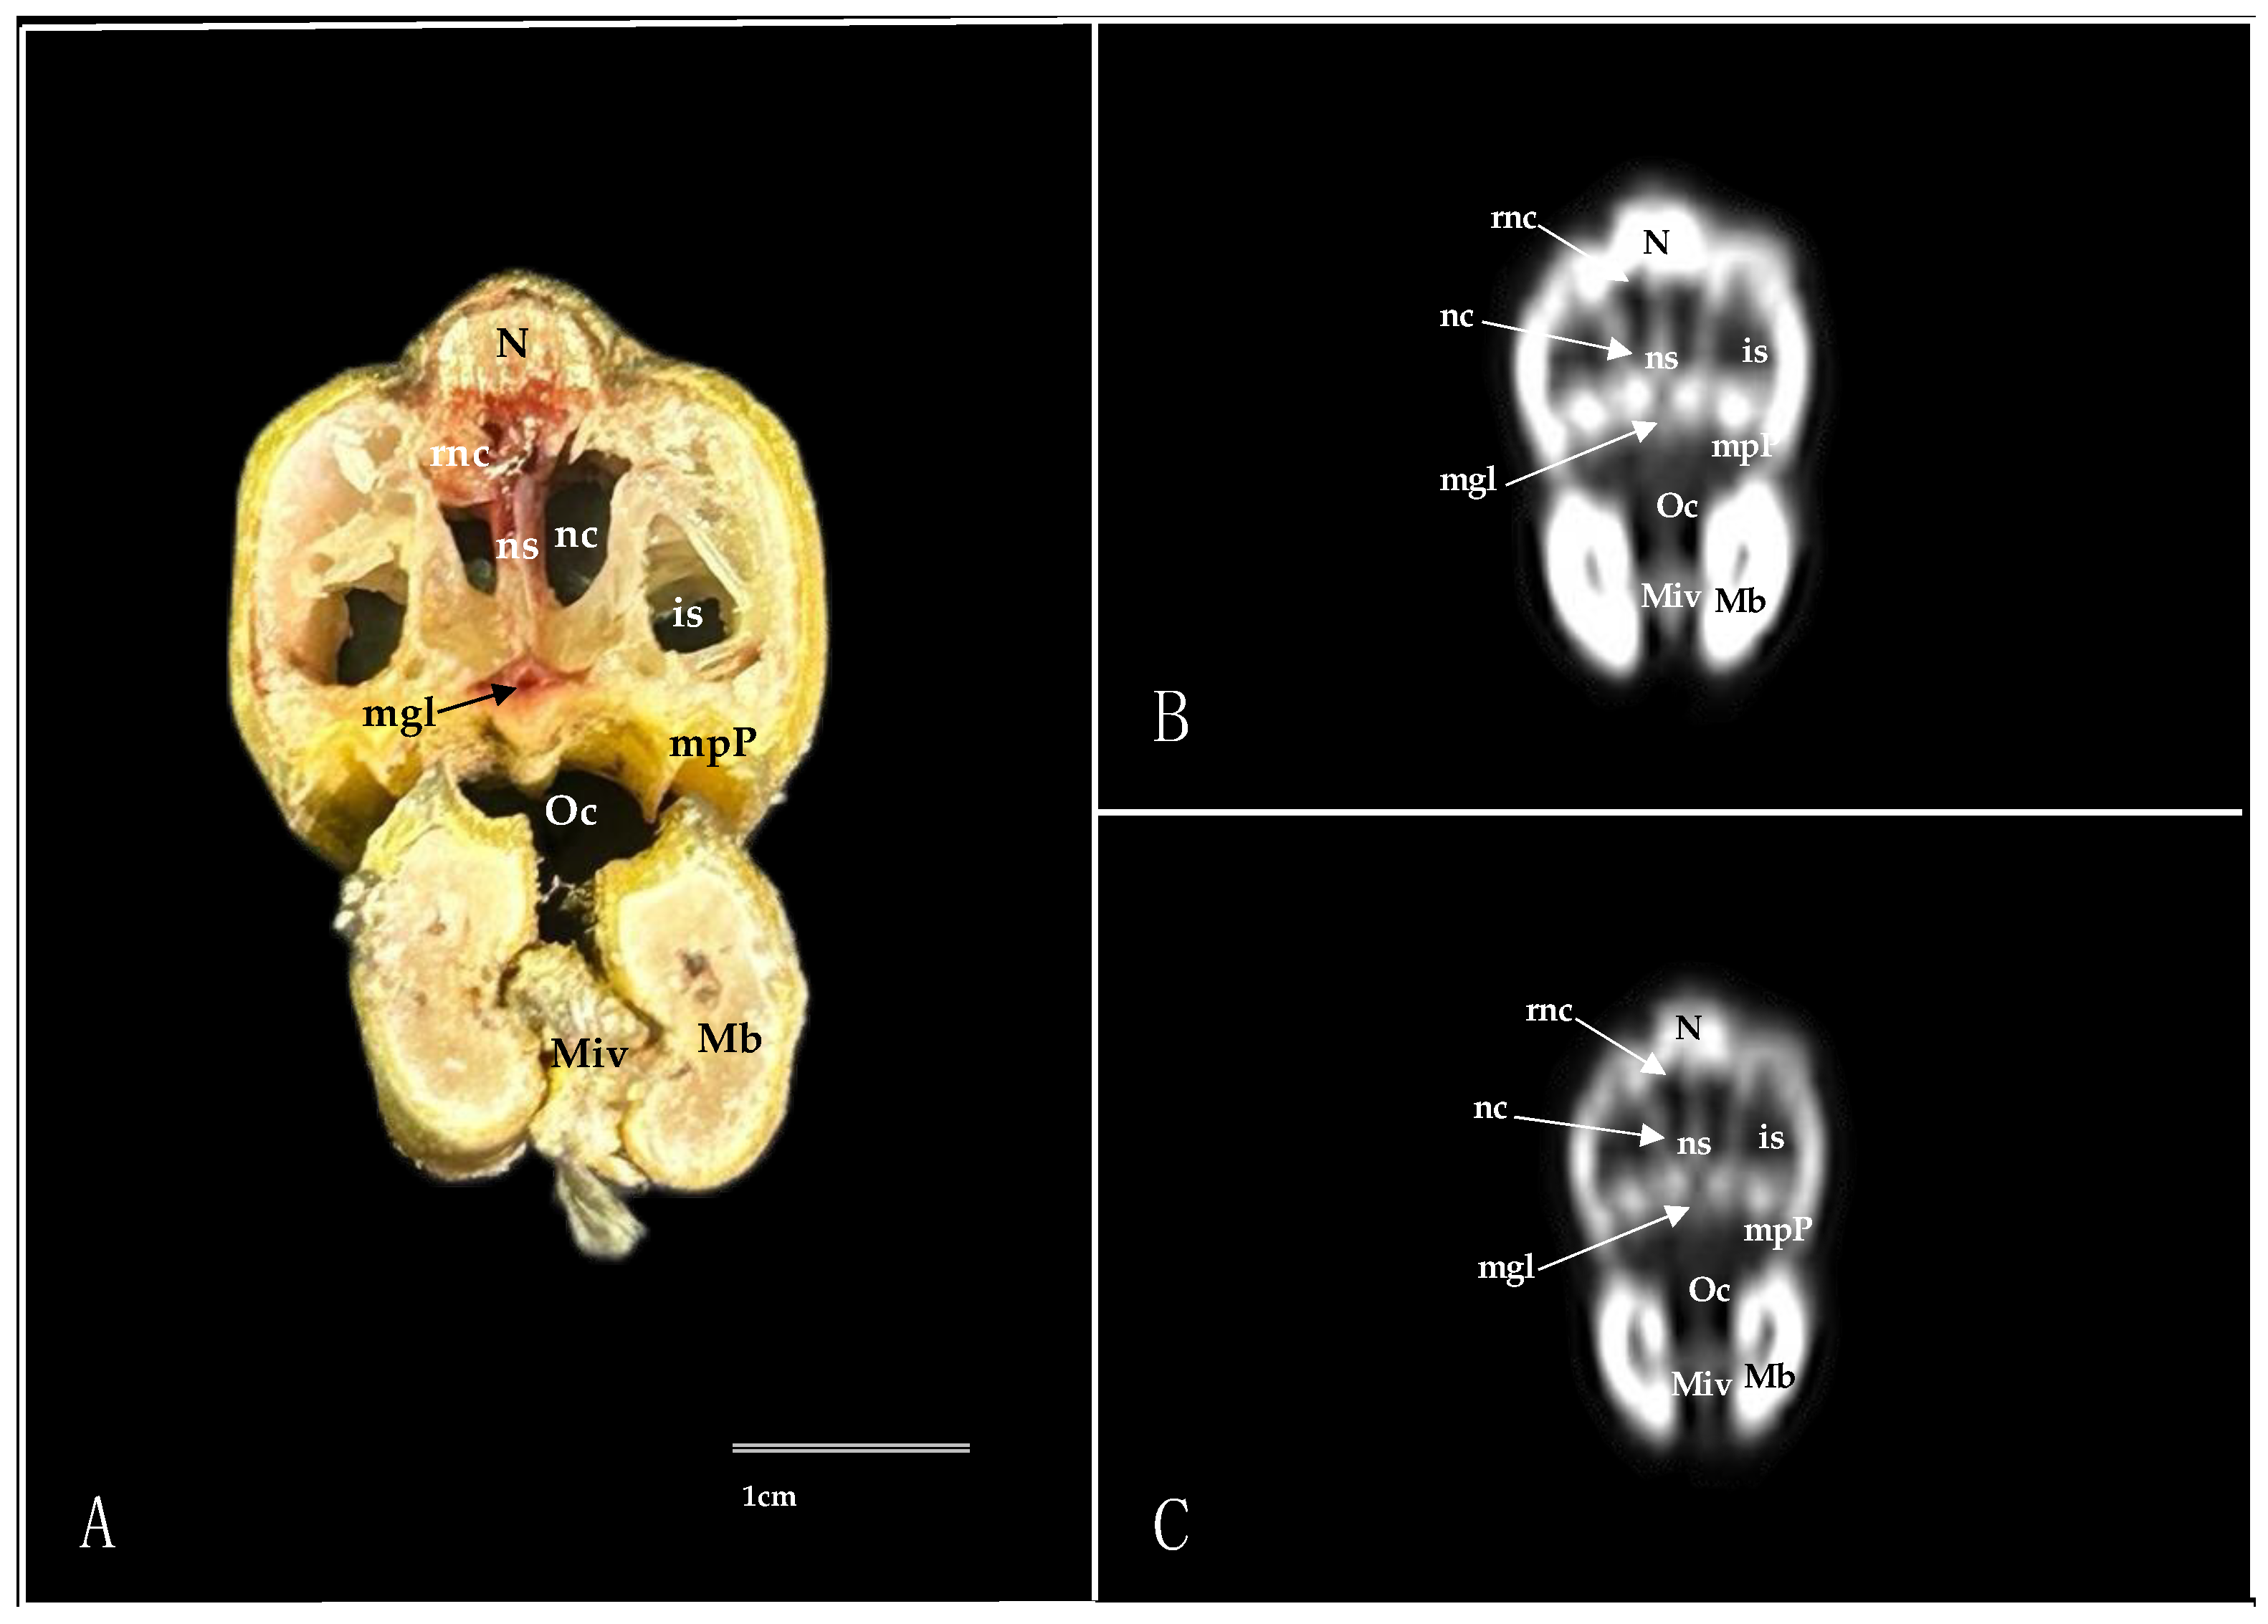

3.1. Anatomical Sections

3.2. Computed Tomography (CT)